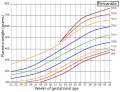

Placenta weight by gestational age[59] -